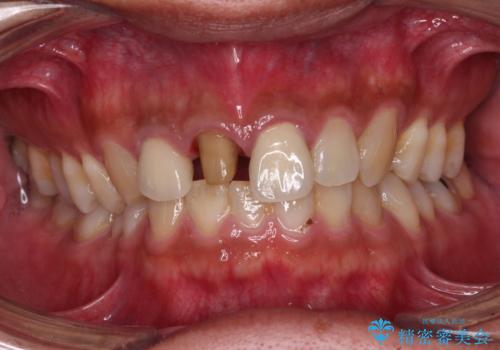

- 前歯の変色した歯を治したいことを主訴として来院された患者様です。

数年前、外傷により両隣の歯とともに根管治療を行い、その後両隣の歯はオールセラミッククラウンにて補綴したそうです。

時間の経過とともに、セラミックにしなかった当該歯の変色が目立つようになり、オールセラミッククラウンにて補綴することとしました。